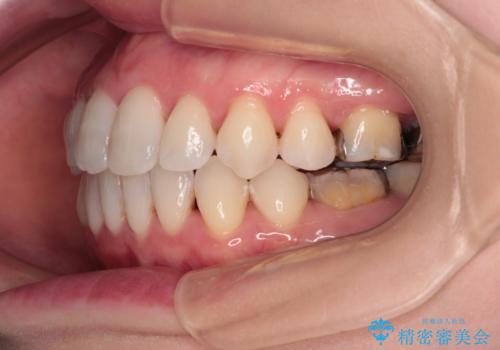

イレギュラーな大臼歯抜歯矯正であったため、治療期間の長期化が想定されましたが、何とか3年ちょうどで終えることができました。

今後は目立っている銀歯を中心にセラミッククラウンなどへ交換していく予定です。